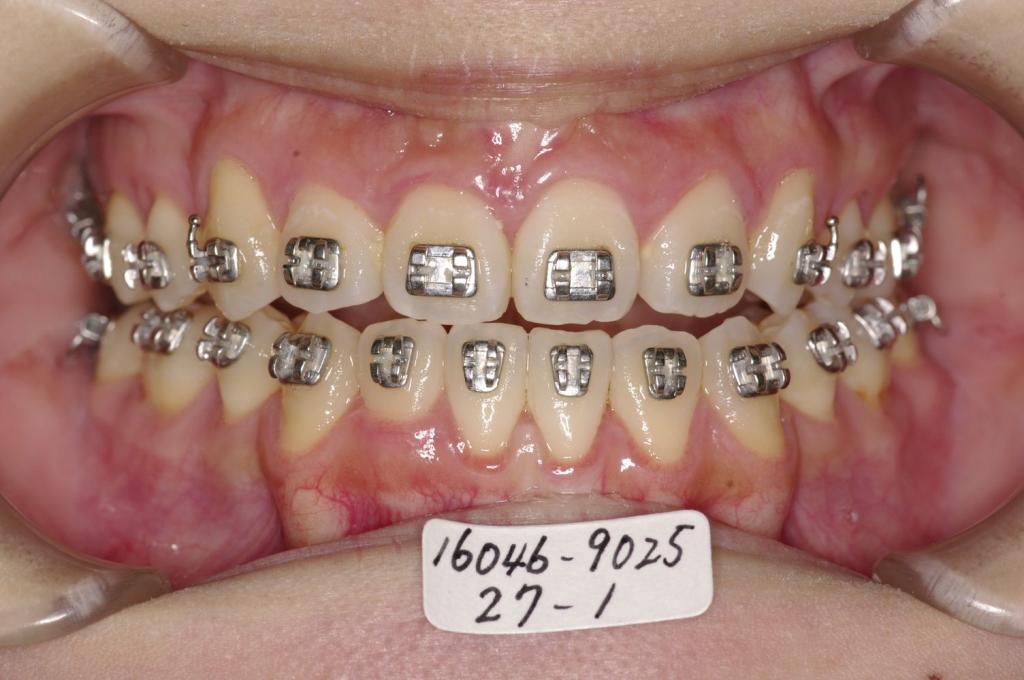

- 顎、顔の歪みの矯正治療

- 上手く咬めない、顎の位置が分からない